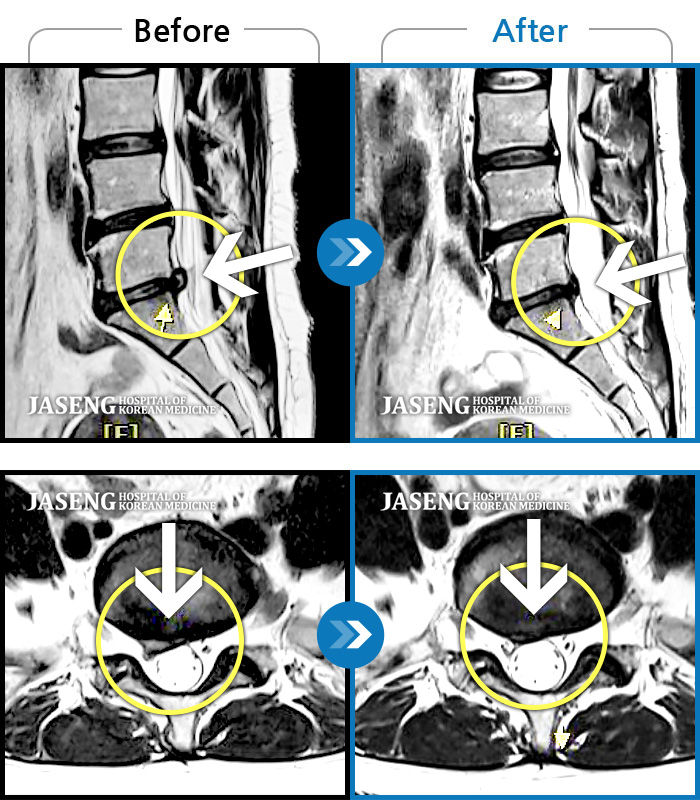

허리디스크

도움받은 사례

광주 · 장영우 원장

양측 허리 통증과 좌측 허벅지부터 발바닥까지 송곳으로 찌르는 듯한 통증 지속되어 내원하셨습니다.

촬영시기

2023.12.26 ~ 2024.12.05

2024.12.12